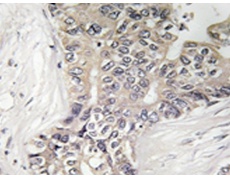

IHC positive control: |

Human liver carcinoma tissue |

IHC Recommend dilution: |

50-100 |